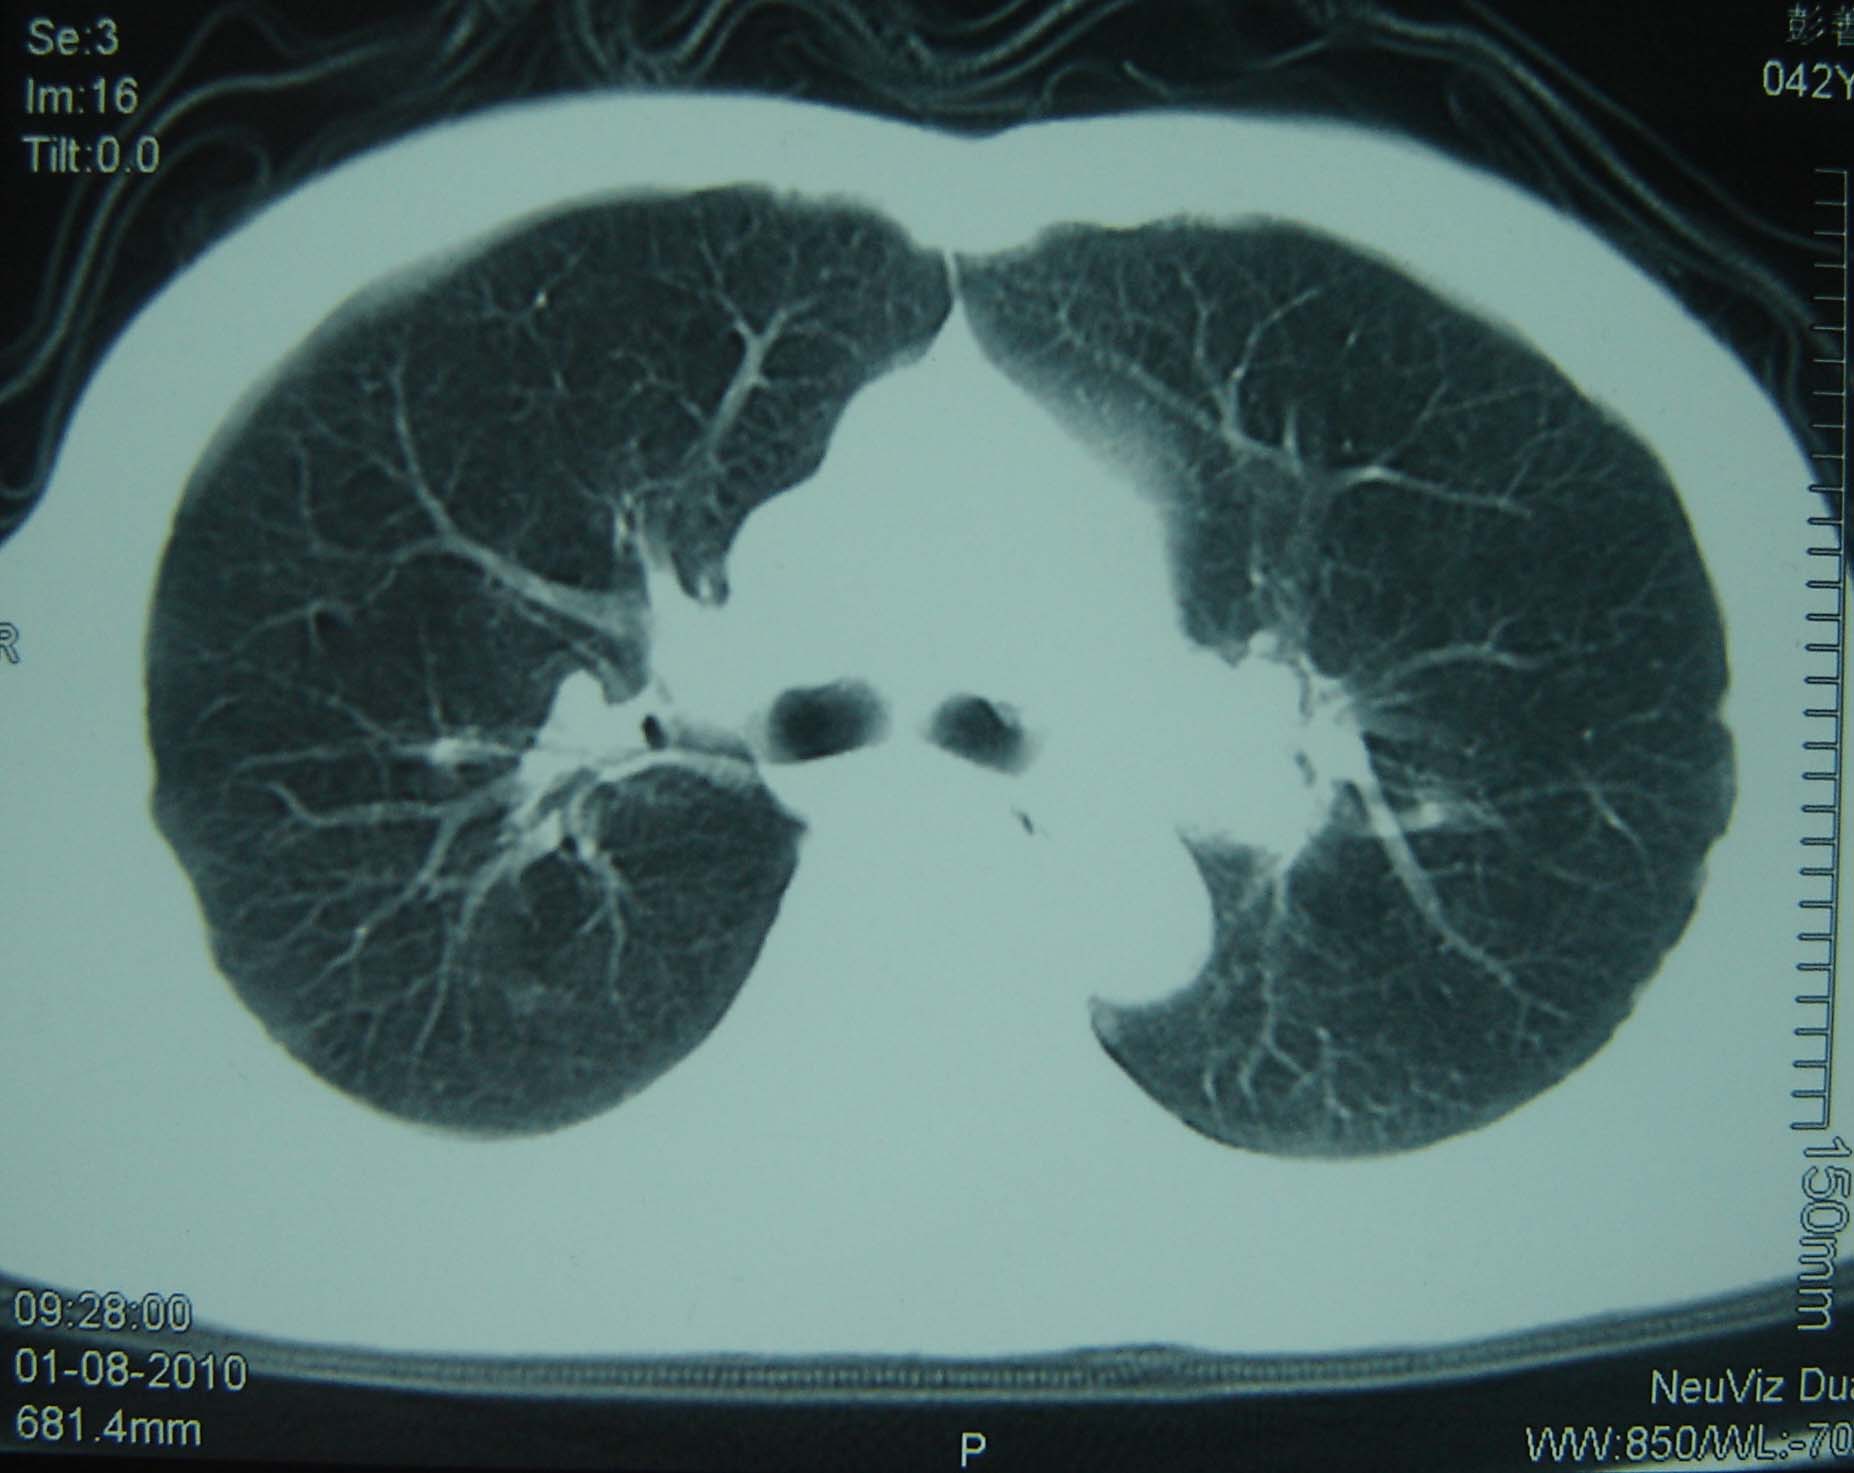

男 、43岁,咳嗽胸痛,装修工,平时接触粉尘较多,有吸烟史10多年,纤维支气管镜检查未发现异常,胃镜、腹部b超检查亦未发现异常,颈部淋巴结活检未发现肿瘤细胞。

不能排除转移,如果不能找到原发灶,只有短期随访。

结节病?转移瘤?

结节病。

转移瘤?

1)考虑双肺及胸膜多发性转移瘤。2)肺气肿。

双肺结节病。